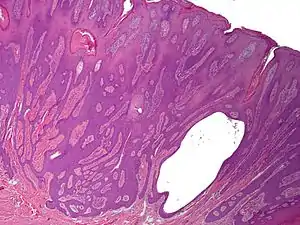

Syringofibroadenoma

Syringofibroadenoma is a cutaneous condition characterized by a hyperkeratotic nodule or plaque involving the extremities.[1]:668